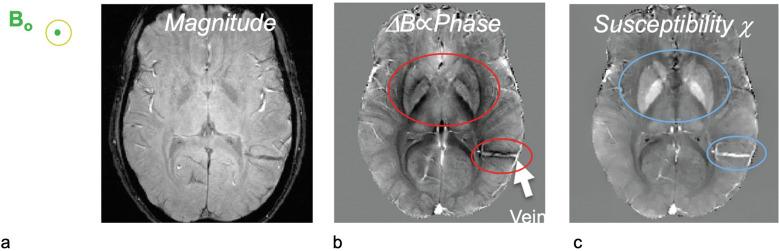

The metabolic rate of oxygen (MRO) is fundamental to tissue metabolism. Determination of MRO demands knowledge of the arterio-venous difference in hemoglobin-bound oxygen concentration, typically expressed as oxygen extraction fraction (OEF), and blood flow rate (BFR). MRI is uniquely suited for measurement of both these quantities, yielding MRO in absolute physiologic units of µmol O min/100 g tissue. Two approaches are discussed, both relying on hemoglobin magnetism. Emphasis will be on cerebral oxygen metabolism expressed in terms of the cerebral MRO (CMRO), but translation of the relevant technologies to other organs, including kidney and placenta will be touched upon as well. The first class of methods exploits the blood's bulk magnetic susceptibility, which can be derived from field maps. The second is based on measurement of blood water T, which is modulated by diffusion and exchange in the local-induced fields within and surrounding erythrocytes. Some whole-organ methods achieve temporal resolution adequate to permit time-series studies of brain energetics, for instance, during sleep in the scanner with concurrent electroencephalogram (EEG) sleep stage monitoring. Conversely, trading temporal for spatial resolution has led to techniques for spatially resolved approaches based on quantitative blood oxygen level dependent (BOLD) or calibrated BOLD models, allowing regional assessment of vascular-metabolic parameters, both also exploiting deoxyhemoglobin paramagnetism like their whole-organ counterparts.

氧代谢率(MRO)是组织代谢的基础。要确定 MRO,需要了解血红蛋白结合氧浓度的动静脉差异,通常以氧提取分数(OEF)和血流速率(BFR)表示。MRI 非常适合测量这两个量,以绝对生理单位(每 100 克组织 100 微摩尔氧/分钟)测量 MRO。本文讨论了两种方法,都依赖于血红蛋白的磁性。重点将放在以脑 MRO(CMRO)表示的脑氧代谢上,但也将涉及将相关技术转化为其他器官,包括肾脏和胎盘。第一类方法利用血液的整体磁化率,可以从磁场图中得出。第二种方法基于测量血液水 T1,这受红细胞内和周围局部诱导场中的扩散和交换调制。一些整体器官方法可以实现足够的时间分辨率,以允许在扫描器中进行脑能量学的时间序列研究,例如在脑电图(EEG)睡眠阶段监测的同时进行睡眠。相反,为了提高空间分辨率,已经开发出了基于定量血氧水平依赖(BOLD)或校准 BOLD 模型的空间分辨率方法,允许对血管代谢参数进行区域评估,这些方法也像它们的整体器官对应物一样利用去氧血红蛋白的顺磁性。